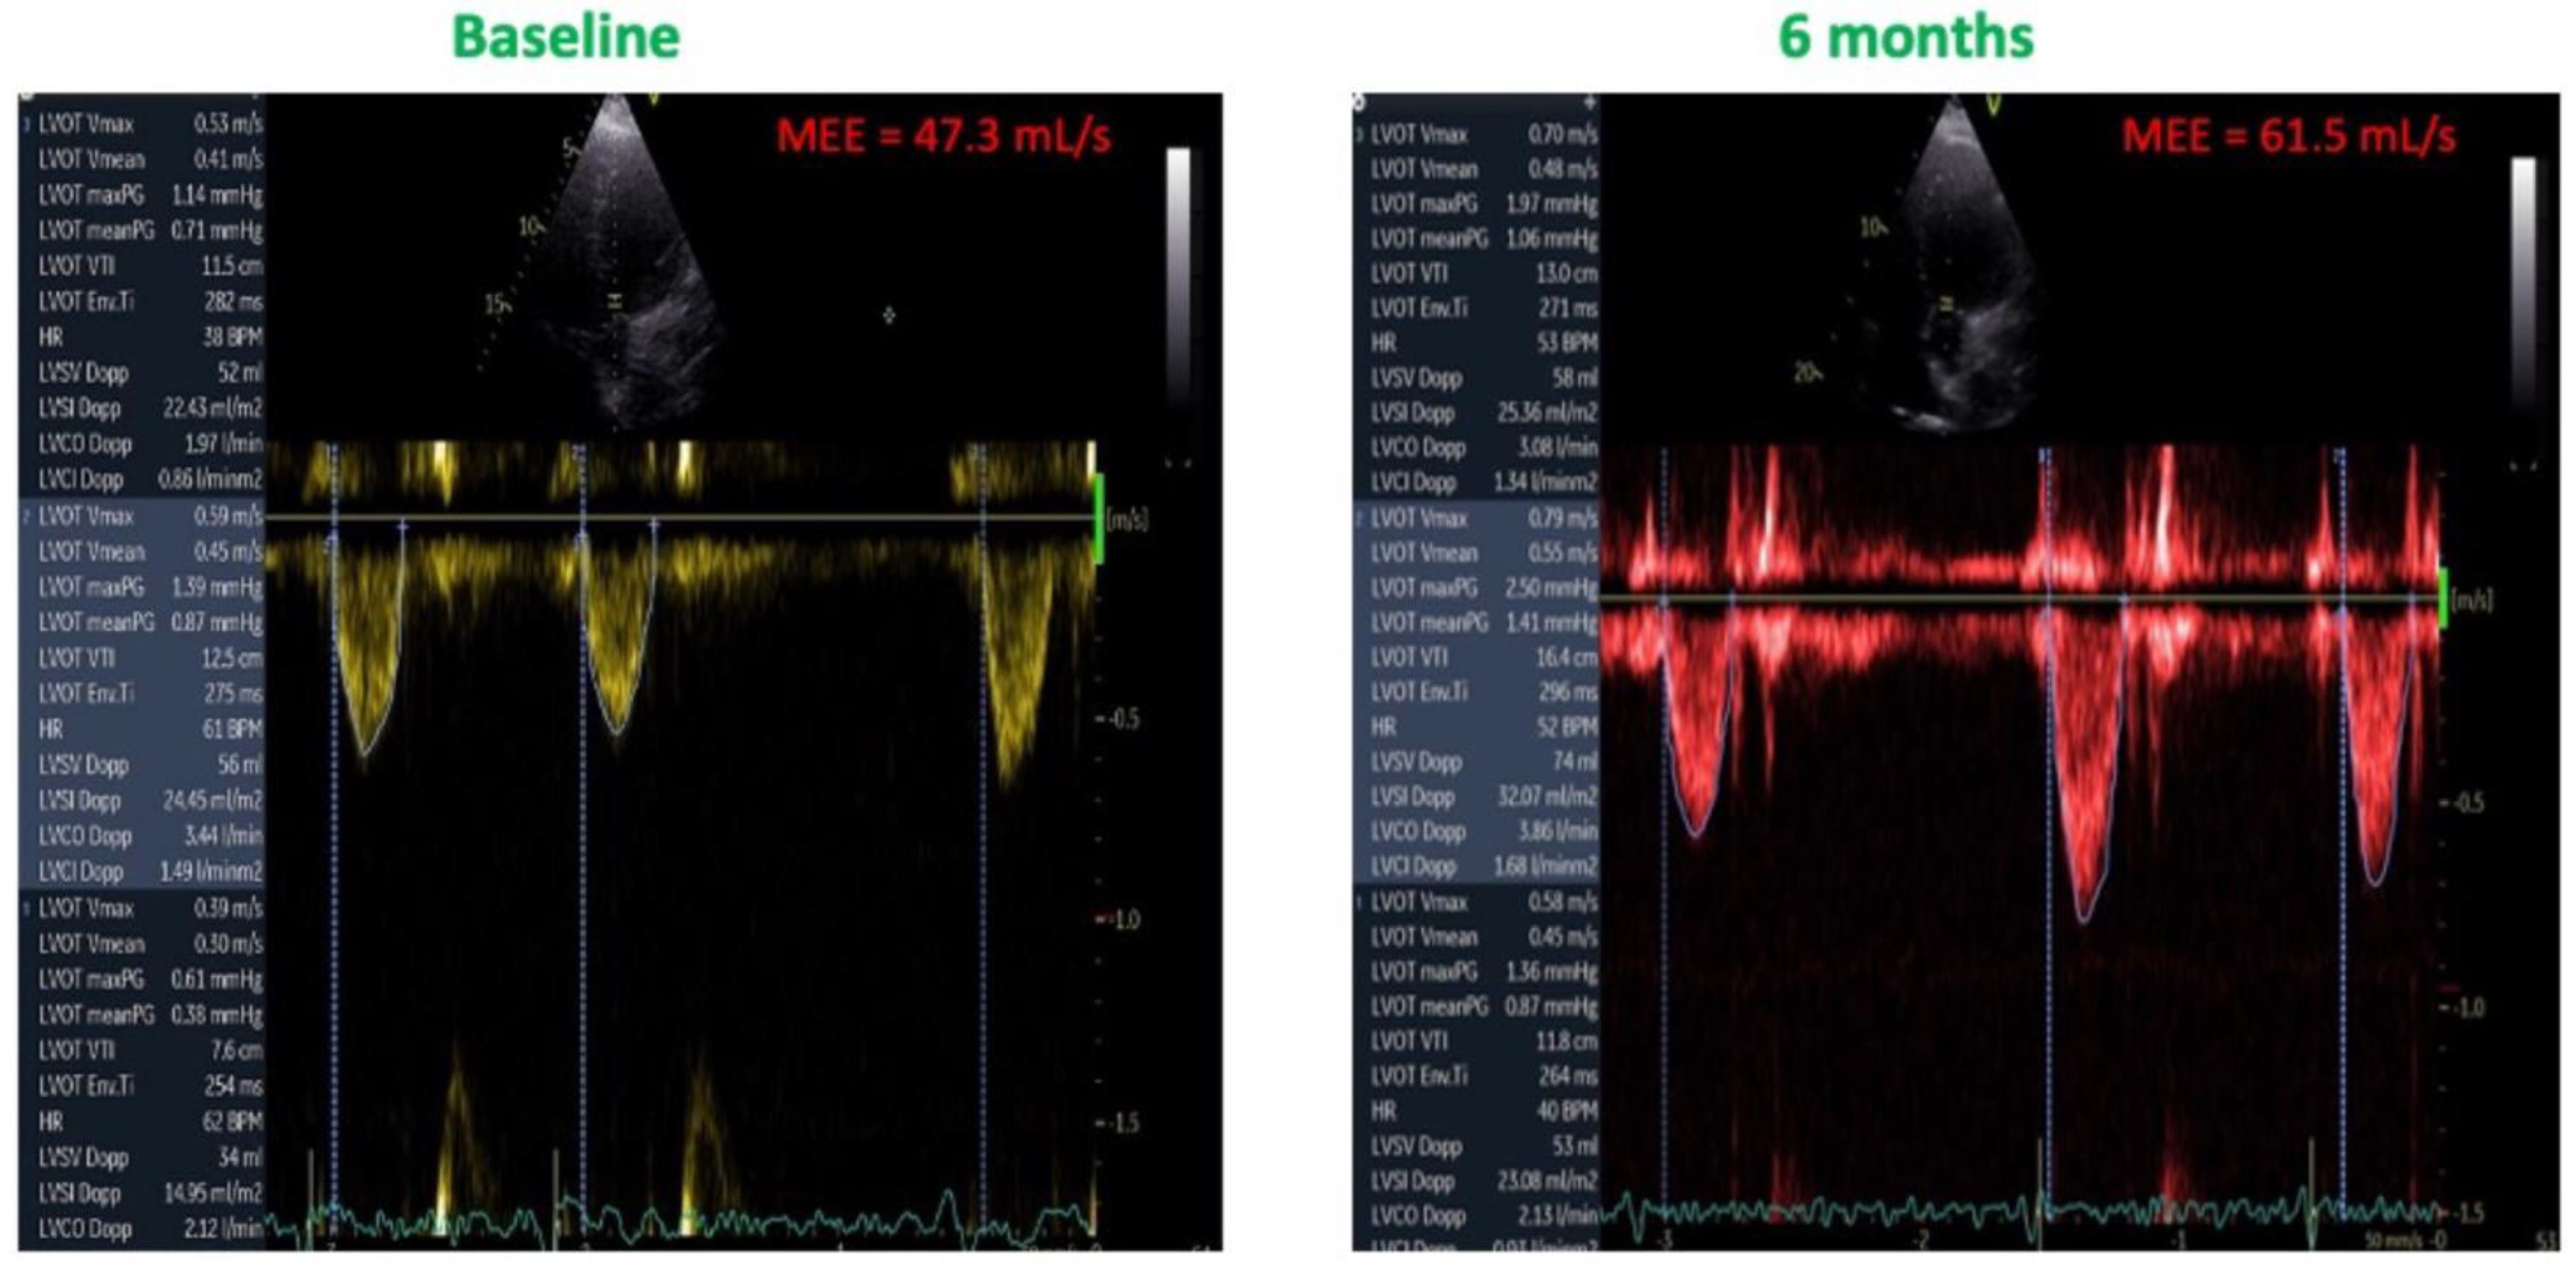

3.3. Effects of CCM on MEE